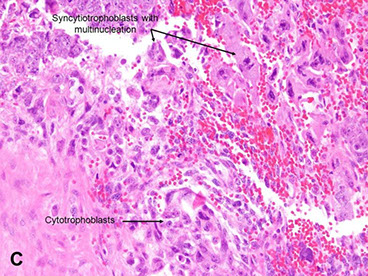

Micro: Biphasic (all are cytokeratin and GATA3 +)

- cytotrophoblasts (CT, small, round mononucleated cells c clear cytoplasm) and intermediate trophoblasts (rIT, edder cytoplasm, has morphology of other 2 types??)

- syncytiotrophoblasts (ST, multinucleated) c variable atypia, pleomorphism, hyperchromasia, big nucleoli

Choriocarcinoma, cytologic features